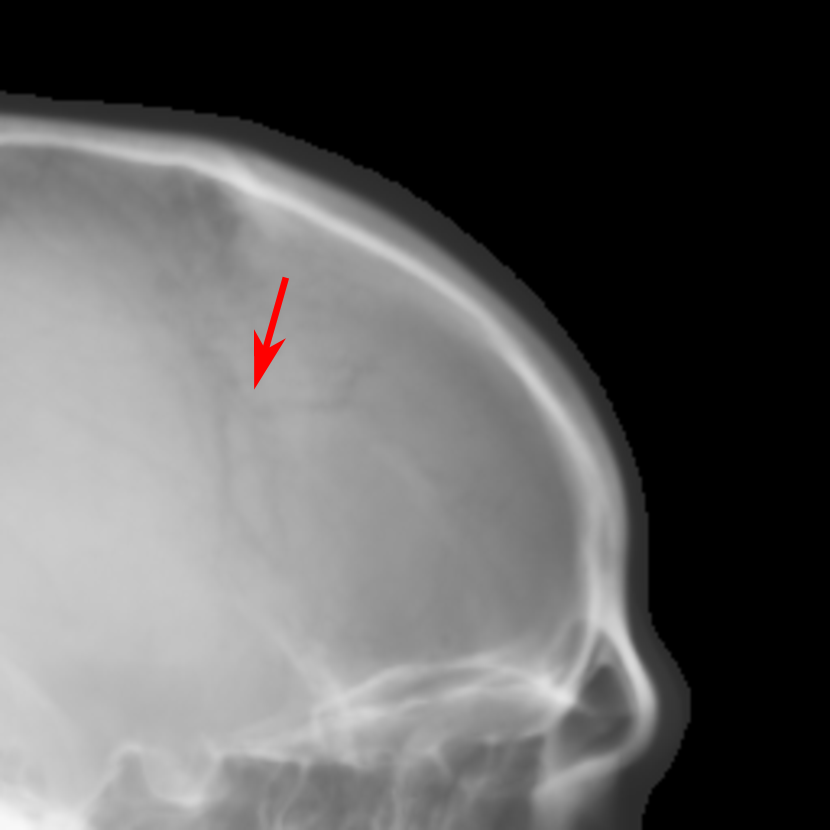

Refer to caption

Fig. 9: Intensity profiles of a chosen line from Figs. 8(a)-(g). The position of the line is marked in Fig. 8(a). The major crests and troughs in the curve of our proposed method are marked by CisubscriptC𝑖\text{C}_{i} and TisubscriptT𝑖\text{T}_{i} where i=1,2,3,4𝑖1234i=1,2,3,4, respectively. Their positions are indicated by the red-dashed and blue-dotted vertical lines respectively. The soft tissue region is marked by S.

For quantification, the intensity profiles of a chosen line from Figs. 8(a)-(g), the position of which is marked in Fig. 8(a), are plotted in Fig. 9. The major crests and troughs in the curve of our proposed method are marked by CisubscriptC𝑖\text{C}_{i} and TisubscriptT𝑖\text{T}_{i} where i=1,2,3,4𝑖1234i=1,2,3,4, respectively. At the position C4subscriptC4\text{C}_{4}, it is clear that the line profiles of orthogonal RayCast and perspective RayCast have low contrast. The profile of MIP100 has high contrast for the crests and troughs. However, the soft tissue part marked by S has too large intensity. The profile of CycleGAN has high contrast as well. Nevertheless, it also introduces undesired crests and troughs, for example, those between T4subscriptT4\text{T}_{4} and C4subscriptC4\text{C}_{4}. In addition, the position of C4subscriptC4\text{C}_{4} is also shifted. Compared with the original orthogonal RayCast, the profile of orthogonal RayCast from the enhanced volume has better contrast at all the positions of C1C4subscriptC1subscriptC4\text{C}_{1}-\text{C}_{4}. With the original sigmoid transform, the contrast is further enhanced. However, at the soft tissue part marked by S, it almost has a constant value. The profile of our proposed modified sigmoid transform overlaps with that of the original sigmoid transform except for the soft tissue part, where the contrast of the soft tissue is brought back.